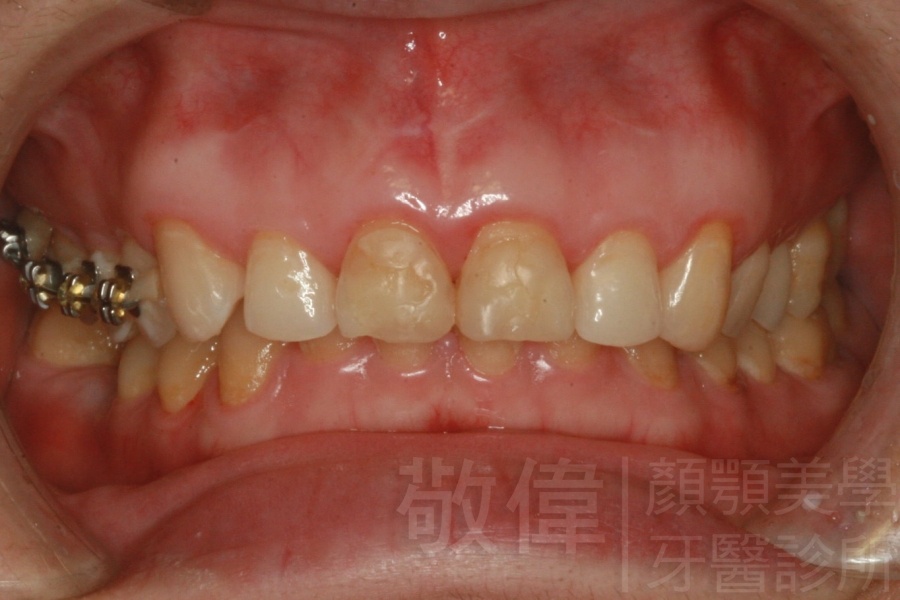

| 8 | 前牙美容 | 快速矯正之美容晶瓷貼片及晶鑽瓷冠 | ||

| 9 | 前牙美容 | 矯正+美容晶瓷貼片 | ||